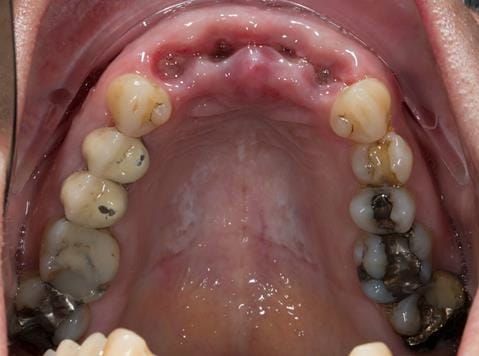

- UR2 peri-radicular periodontitis with a peri-radicular area on the root apex. Retrograde amalgam filling from a previous apicectomy. No visible root canal or root canal filling. Large circumferential marginal gap between the crown and tooth. Large post and core present. Very little tooth structure remaining resulting in a fragile tooth with increased potential for fracture.

- UR1 peri-radicular periodontitis with a small peri-radicular area on the root apex with wide blunderbuss apex. Radio-opaque root canal filling present approximately 3 mm short of the radiographic apex. Large circumferential marginal gap between the crown and tooth. Large post and core present. Very little tooth structure remaining resulting in a fragile tooth with increased potential for fracture.

- UL1 peri-radicular periodontitis with a peri-radicular area on the root apex. Retrograde amalgam filling from a previous apicectomy. Visible root canal space with no sign of root canal filling. Large circumferential marginal gap between the crown and tooth. Large post and core present. Very little tooth structure remaining resulting in a fragile tooth with increased potential for fracture.

- UL2 peri-radicular periodontitis with a peri-radicular area on the root apex. No visible root canal or root canal filling. Large circumferential marginal gap between the crown and tooth. Large post and core present. Very little tooth structure remaining resulting in a fragile tooth with increased potential for fracture.

- High smile line showing gum above gingival zeniths of upper front teeth when smiling. Aesthetic failure of the upper four incisors with inflammation of the gingivae and mis-match of the gingival zenith levels.

- Other than the maxillary incisors the remaining dentition was in marginally better condition being moderately to heavily restored. Many will probably require replacement and restoration from time to time mainly from wear and tear owing to occlusal forces.